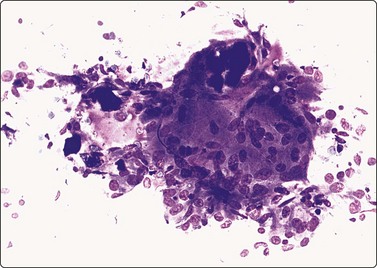

image

Fig. 6.41 Cystic papillary carcinoma

Fluid aspirated from cystic PC is uncharacteristic, brown or resembles altered blood. The diagnosis can easily be missed if well-preserved epithelial cells are scarce (Fig. 6.41).30,31,71 Presence of numerous macrophages, with many in cohesive clusters, should raise a suspicion of PC. Some of these cells are probably degenerating tumor cells exfoliated from the cyst lining (Fig. 6.42). They may represent foam cell metaplasia in tumor cells, and careful scrutiny will usually reveal nuclear features of PC. Large cell size, pseudoinclusions, nuclear grooves, and multiple well-defined vacuoles in atypical histiocytoid cells favor a diagnosis of PC.186